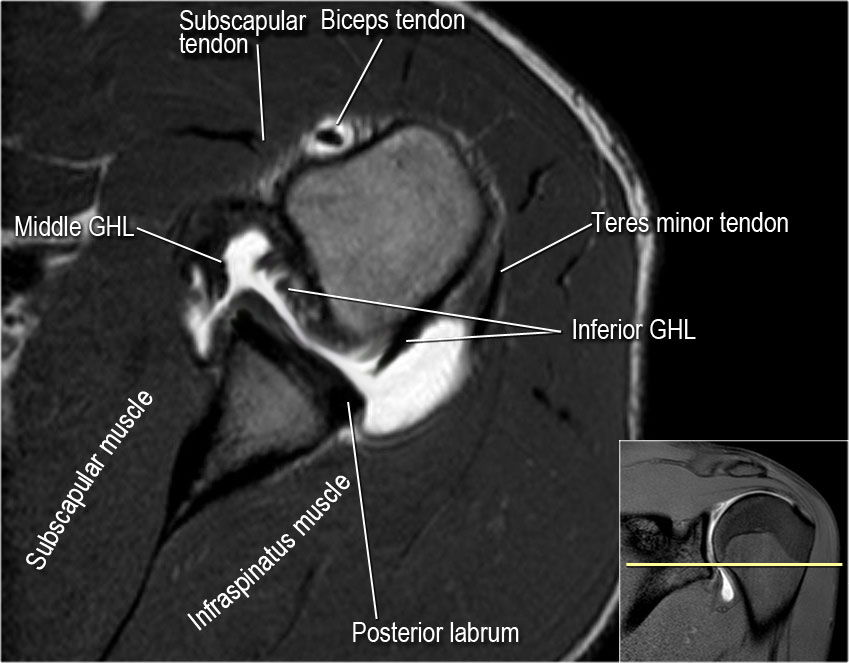

Radiologists primarily perform shoulder imaging to assess injuries within the shoulder joint.

The tendons that connect the biceps muscle to the shoulder joint in two places are called the proximal biceps tendons. Shoulder tendonitis is inflammation of your rotator cuff or bicep tendons, often caused by overuse of the arms such as in baseball, weight lifting, and tendonitis of your shoulder is an inflammation of your rotator cuff and/or biceps tendon. Biceps tendinitis is the inflammation of the biceps tendon may due to impingement or attrition. Bicipital tendinitis causes pain in the biceps tendon that is aggravated by shoulder flexion or resisted supination of the forearm. Radiologists primarily perform shoulder imaging to assess injuries within the shoulder joint. When most people think of the shoulder anatomy, they think of the deltoids. In cases of serious or constant overuse, a tendon may fray and eventually tear. Biceps) heads and thus two attachments around the shoulder. Repetitive overhead motion of the arm initiates or exacerbates the symptoms. The biceps tendon is a source of pain for many people with shoulder problems. It is one of the most mobile joints in the human body, at the cost of joint stability. Inflammation of the biceps tendon (tendinitis m biceps brachii) anatomy: 2, biceps tendon (long head).